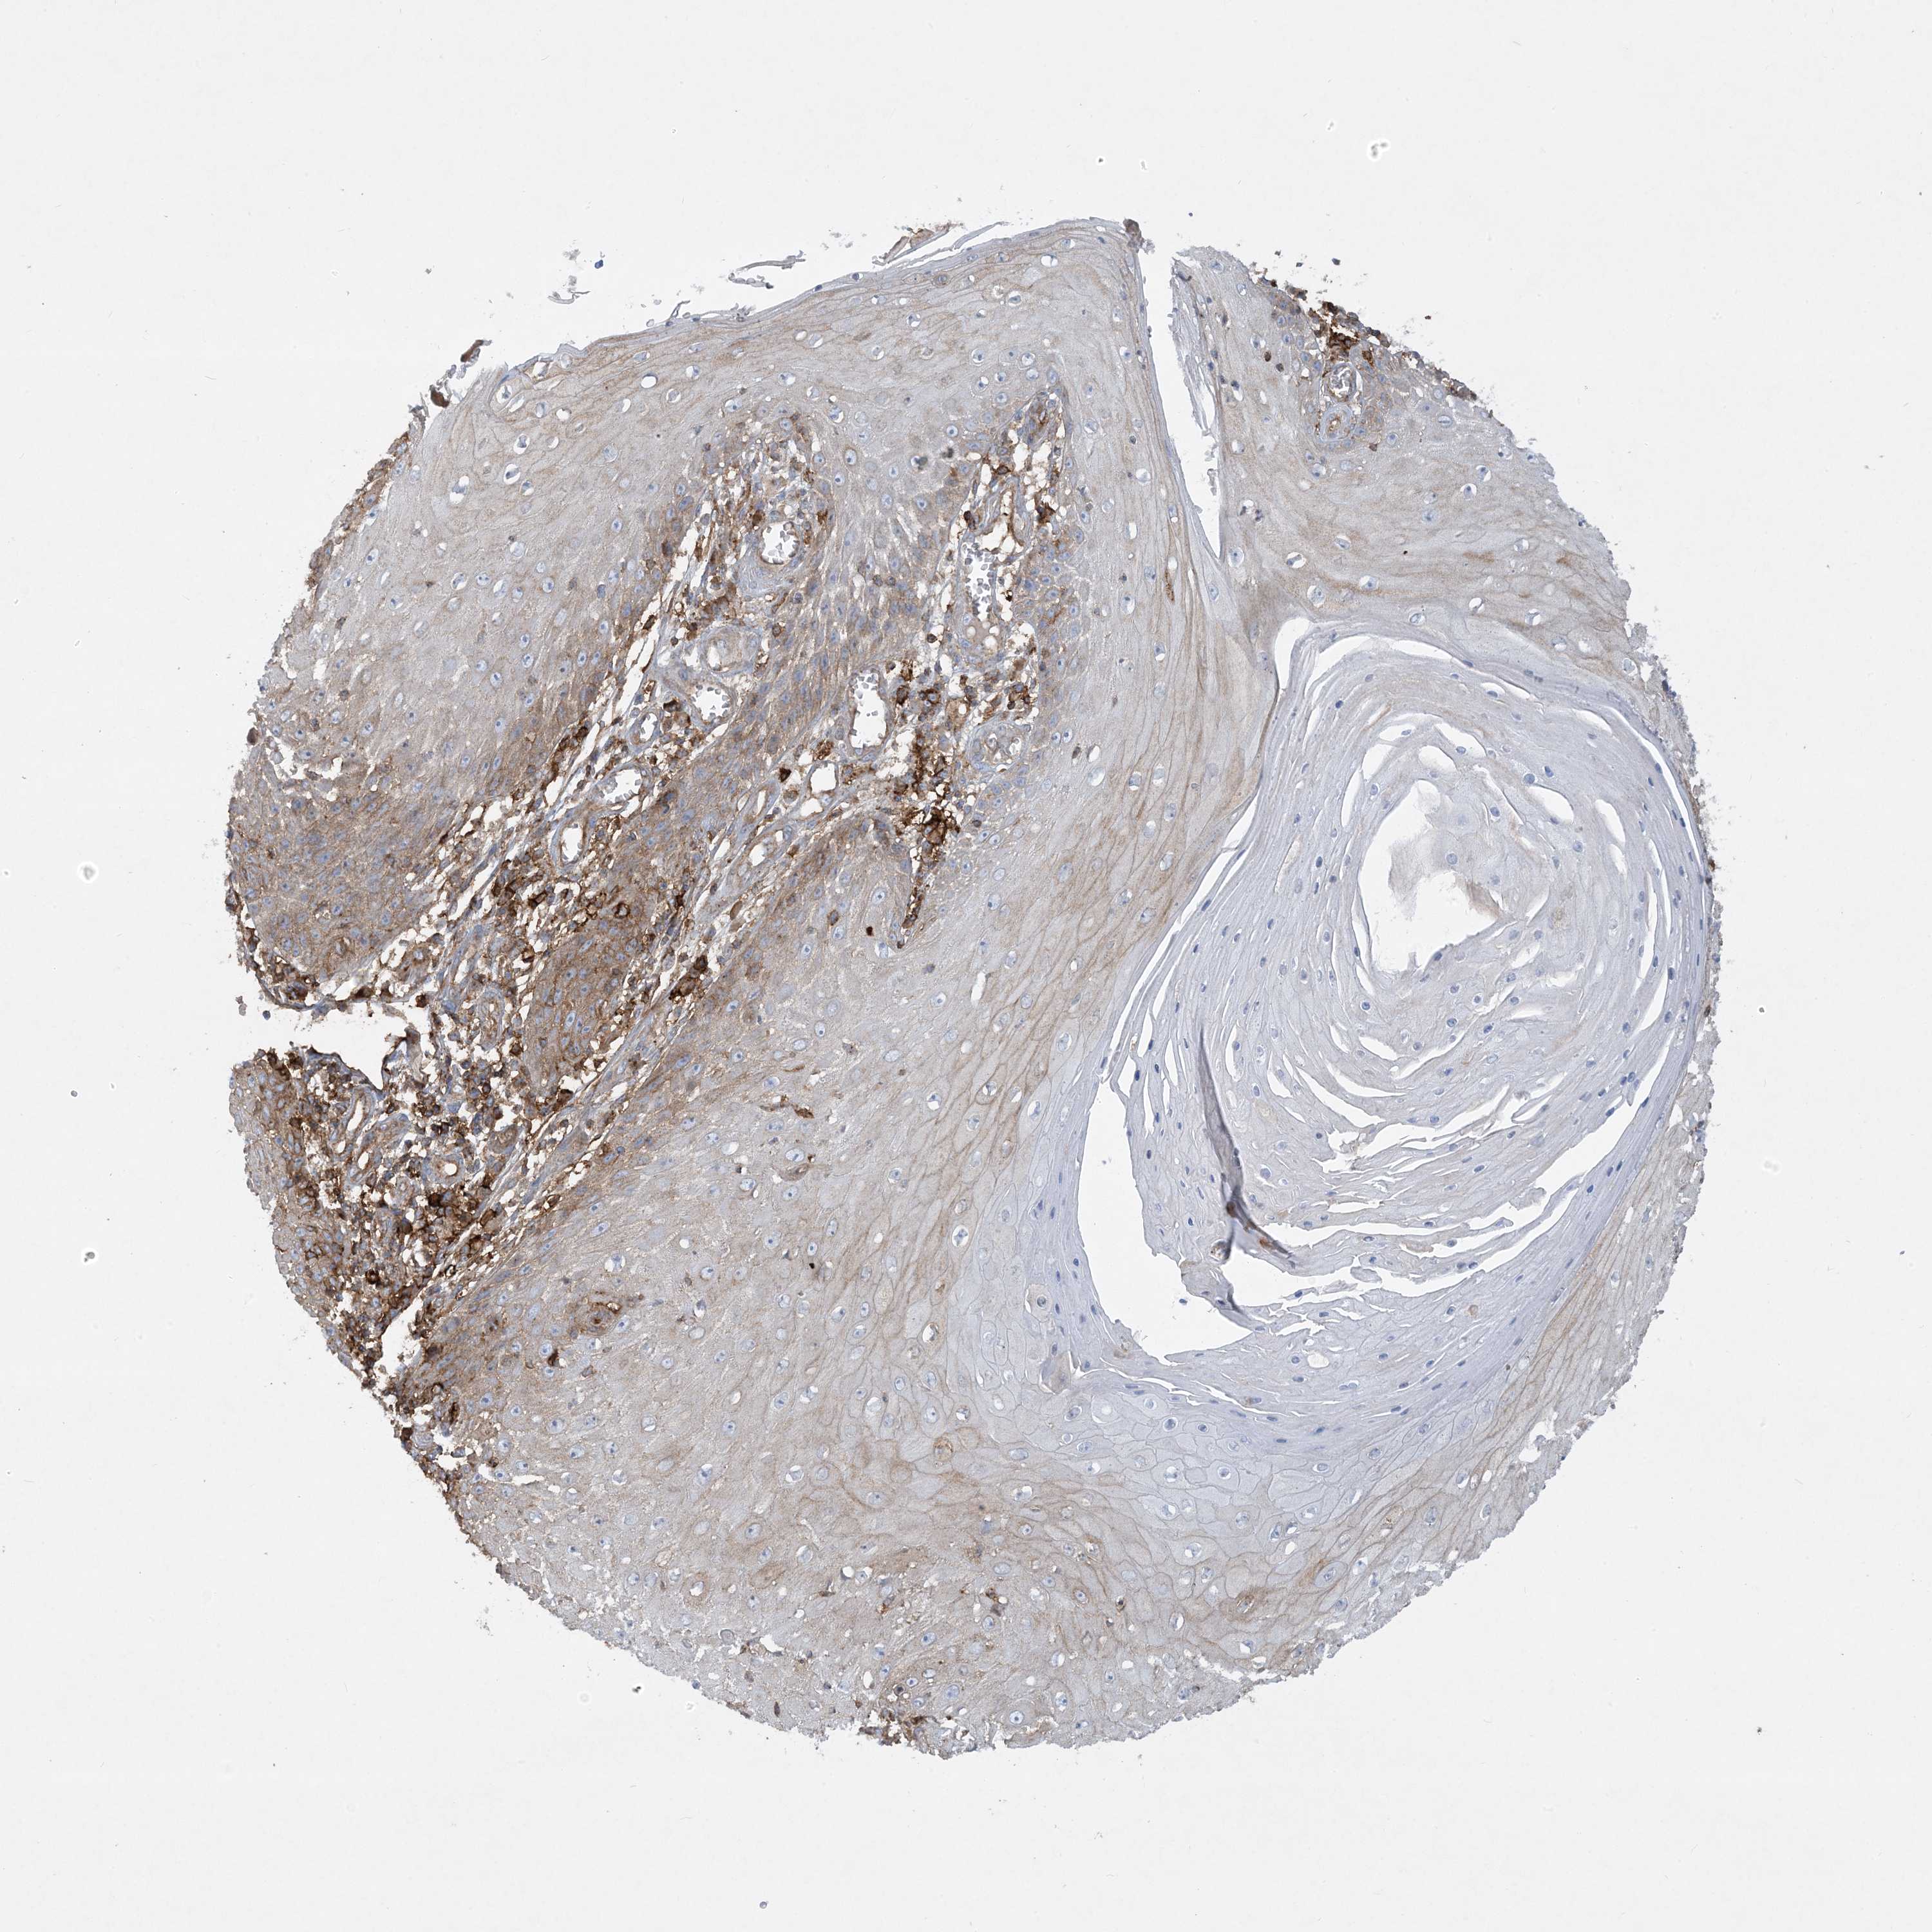

SKIN CANCER - Protein expressioni

A mouse-over function shows sample information and annotation data. Click on an image to view it in a full screen mode. Samples can be filtered based on level of antibody staining by selecting one or several of the following categories: high, medium, low and not detected. The assay and annotation is described here.

Antibody staining in the annotated cell types in the current human tissue is reported as not detected, low, medium, or high, based on conventional immunohistochemistry profiling in selected tissues. This score is based on the combination of the staining intensity and fraction of stained cells.

Each image is clickable and will lead to virtual microscopy that enables deeper exploration of all samples and also displays staining intensity scores, fraction scores and subcellular localization as well as patient and tissue information for each sample.

Antibody CAB024589

Staining

Medium

Intensity

Moderate

Quantity

75%-25%

Location

Cytoplasmic/membranous

Squamous cell carcinoma, NOS